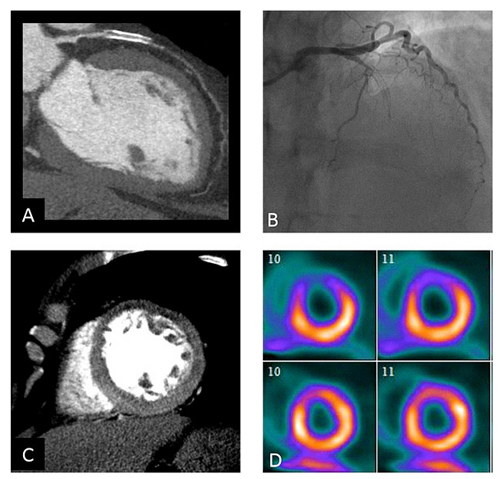

図1 評価に用いた4種類のイメージングの例

パネルA:CTA画像 左前下行枝(LAD)の100%狭窄

パネルB:ICA画像 左前下行枝(LAD)の100%狭窄

パネルC:CTP画像 基底部前壁(重度),遠位部前壁(重度) 遠位部前壁中隔(中等度),心尖(中程度) 遠位前壁と心尖部には固定性欠損あり

パネルD:灌流障害のSPECT画像 遠位部前壁(重度),遠位部前壁中隔(重度,固定性),心尖(重度) |